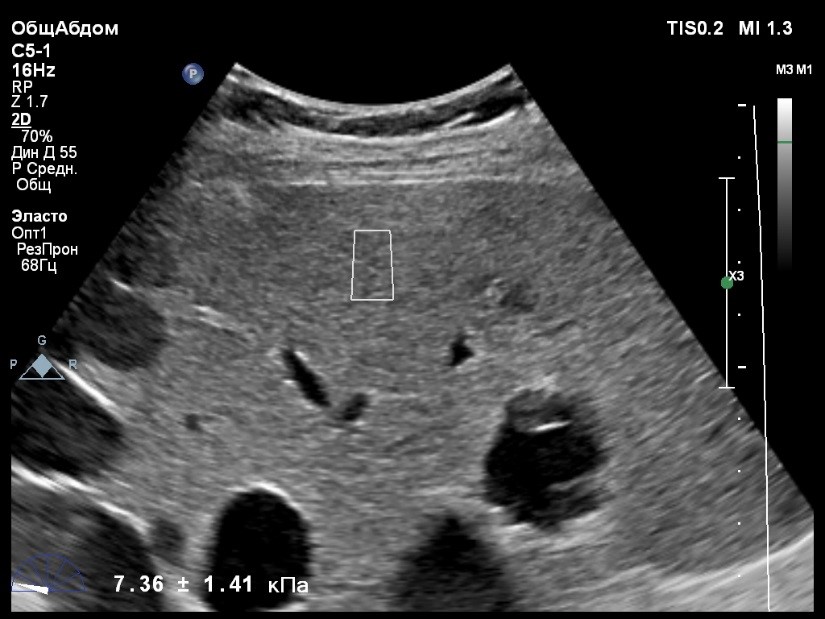

Пациент обратился к доктору с направлением на исследование степени жесткости печени в июне 2017 года. Из истории болезни, пациент страдает Гепатитом С с 2014 года. Лечение не получал. Транзиентная эластография показала не коррективные значения степени жесткости печени по причине сопутствующего поликистоза печени. На момент настоящего исследования, пациент не принимал пищу на протяжении 4 часов, АСТ, АЛТ не превышают патологических значений. Для оценки жесткости была выбрана технология компании Philips ElastPQ (точечная эластография) и прибор компании Philips Epiq 7 Исследование было проведено в соответствии с клиническими рекомендациями для ультразвуковых приборов компании Philips. В результате исследования были получены следующие результаты:

| 1 [7.95] kPa | 2 [8.73] kPa | 3 [8.11] kPa |

| 4 [9.32] kPa | 5 [8.05] kPa | 6 [9.52] kPa |

| 7 [8.66] kPa | 8 [7.36] kPa | 9 [8.54] kPa |

| 10 [8.30] kPa | 11 [6.56] kPa | 12 [7.14] kPa |

| 13 [7.47] kPa | 14 [6.56] kPa | 15 [6.56] kPa |

Стандартное Отклонение [0.85] kPa Медиана Жесткости [8.05] kPa Фактор Качества IQR/Med 10%

Зона интереса расположена на более чем на один сантиметр глубже капсулы, параллельно ходу луча, в середине изображения, в участке печени лишенном кист.

Капсула видна как белая линия перпендикулярная ходу ультразвукового луча, исследования производятся приблизительно в одном и том же сегменте печени.

Стандартное отклонение (2,26 kPA) не превышает 30 процентов от полученного значения (8,54 kPA).

Для интерпретации полученных клинических данных были использованы Рекомендации по проведению эластографии сдвиговой волной для оценки жесткости печени при использовании ультразвуковых аппаратов компании Филипс с примером протокола. Техническая сложность проведения слепой эластометрии печени связана с сопутствующим поликистозом органа и диагностическим методом выбора в данной ситуации является Эластография с возможностью визуального контроля положения контрольного объема. Подготовка пациента соответствовала проводимому исследованию. Представленные слайды проведенного исследования свидетельствуют о правильном техническом исполнении проб, отсутствием в поле контрольного объема кистозных образований, что позволяет заключиться о достоверности полученных измерений. Таким образом, учитывая полученную медиану жесткости на уровне 8,05 кРа (6.56 – 9.52 kPa) и уровень стандартных отклонений не превышающих 30%, полагаю, что уровень степени фиброза соответствует стадии F2. Заведующий отделением УЗД МЦ «Асклепий», Глушенко Д. Е.